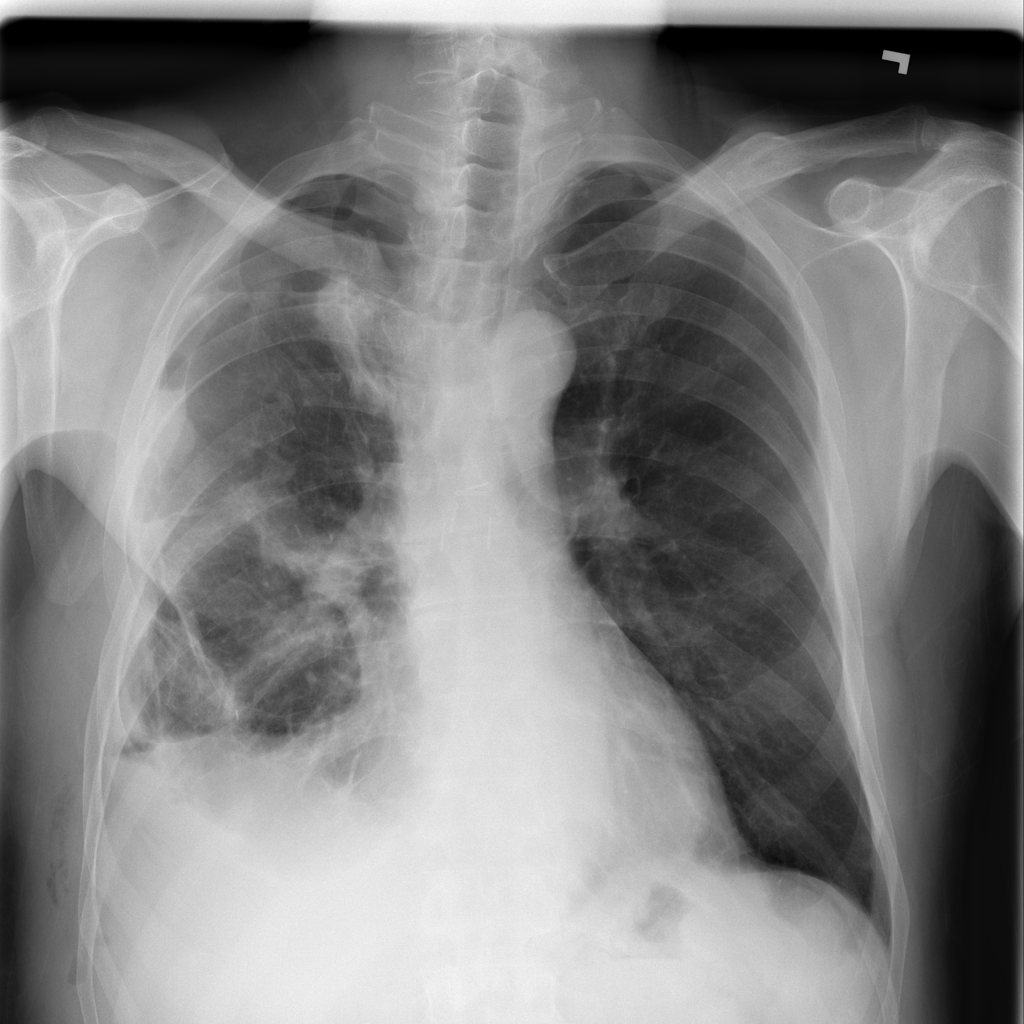

PAT-86C8 · IMG-006Atelectasis

PAT-86C8 · IMG-006

PA